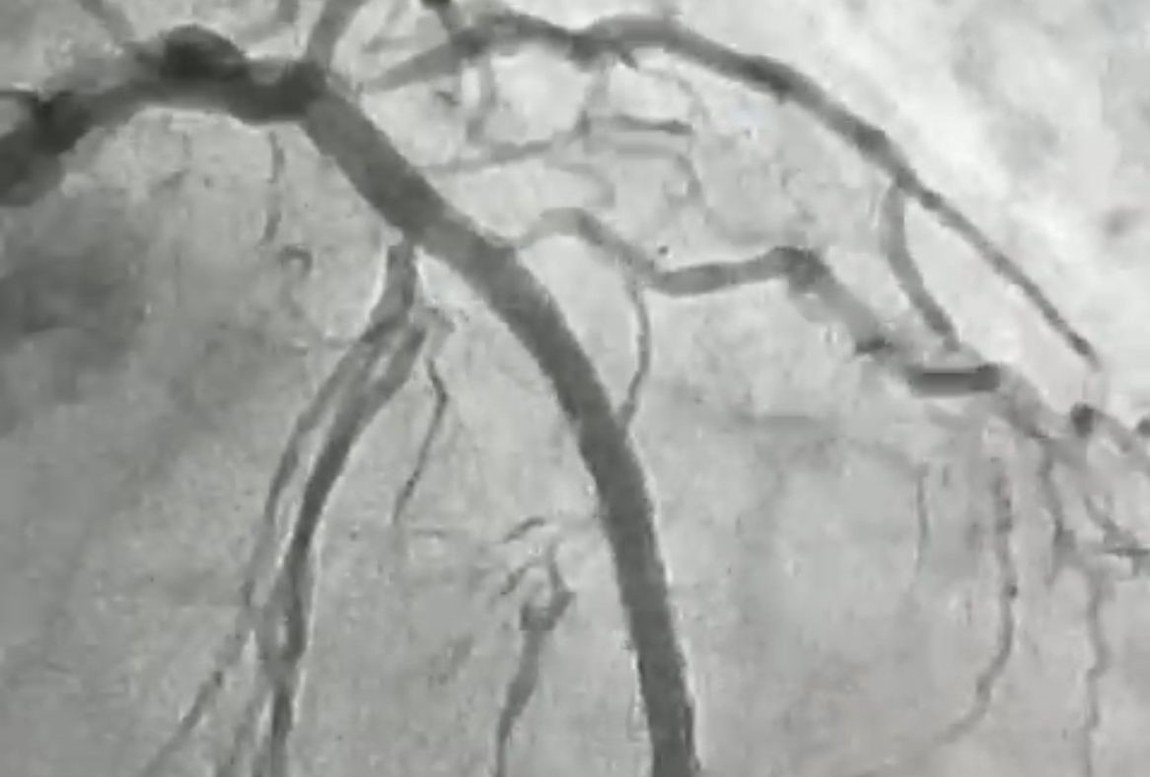

O serviço de Hemodinâmica, instalado no Hospital Regional de Patos e gerenciado pela Fundação Paraibana de Gestão em Saúde (PB Saúde), realizou, nesta semana, mais um procedimento inédito no Sertão da Paraíba, marcando um avanço significativo na oferta de tratamento cardiovascular de alta complexidade na região. Trata-se de uma angioplastia com aterectomia rotacional, técnica conhecida como rotablator, associada à ultrassonografia intracoronariana, um conjunto de métodos utilizados apenas em centros de referência de alto nível no país.

O procedimento foi realizado em uma paciente de 84 anos, moradora de Itaporanga, que apresentava uma lesão grave e altamente calcificada na artéria descendente anterior, considerada a principal artéria do coração. Segundo o cardiologista intervencionista, Jeann Santiago, um dos médicos responsáveis pela realização do procedimento, a condição exigia um tratamento extremamente delicado, com risco elevado, devido à dureza da placa obstrutiva, comparada pelos médicos a uma “pedra” no interior do vaso.

“Para possibilitar a abertura da artéria, a equipe utilizou a aterectomia rotacional, técnica que funciona como uma micro furadeira capaz de desgastar e desobstruir placas de cálcio muito rígidas. Em seguida, com o auxílio do ultrassom intravascular, foi possível medir com precisão a extensão da lesão e determinar o tamanho ideal dos dispositivos a serem implantados. Após a preparação do vaso, foram colocados dois stents farmacológicos, completando o processo de revascularização”, explicou o cardiologista.